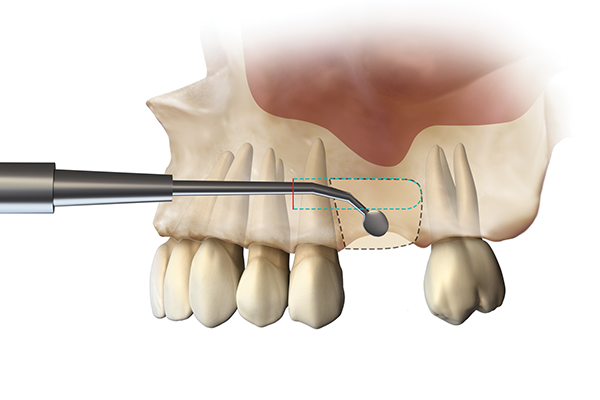

Fig 17. Illustration of SMART method. A full-thickness incision is made at a remote location, and a subperiosteal tunnel is developed to provide laparoscopic access to the site (Fig 17). A subperiosteal pouch is then created to confine the graft without damaging the periosteum (Fig 18).

Figure 17

Fig 18. Illustration of SMART method. A full-thickness incision is made at a remote location, and a subperiosteal tunnel is developed to provide laparoscopic access to the site (Fig 17). A subperiosteal pouch is then created to confine the graft without damaging the periosteum (Fig 18).

Figure 18

For the present case, the SMART method was used to achieve horizontal bone augmentation while preserving the soft-tissue profiles developed using forced eruption. Flap elevation would have resulted in loss of gingival architecture and the residual root of tooth No. 8. A confined subperiosteal tunnel and pouch were developed using the SMART instrumentation and surgical technique to allow the delivery of an anorganic bovine-derived bone mineral and platelet-derived growth factor combination and horizontally augment the labial alveolar bone in area Nos. 6, 7, and 8. The rationale for selecting the biomaterial was based on its low substitution rate and ability to maintain the contours of the augmentation (Figure 13 through Figure 15).55-57 The recombinant platelet-derived growth factor BB was used to stimulate bone formation and favor soft-tissue healing.58-60

The SMART method does not require the use of tenting screws or other space-maintaining devices. The degree of horizontal augmentation is a result of the ability to establish the confines of the tunnel and subperiosteal pouch, so that particle aggregation can be achieved while controlling the dispersion of the graft material.

Because recession was already present on tooth No. 5, the scope of the SMART procedure was extended to horizontally augment adjacent areas that exhibited dehiscences and thin buccal plates (Figure 16). The augmented areas evident in Figure 16 (which can be compared to the preoperative imaging in Figure 4) were accomplished using two remote incisions. It must be emphasized, however, that this procedure may be technique sensitive, and predictable outcomes require training and experience. Unlike lateral subperiosteal techniques, the SMART method is based on the development of a laparoscopic tunnel from a remote incision to access the graft site. A subperiosteal pouch is subsequently created to confine the biomaterial particles (Figure 17 and Figure 18). This approach ensures that surgical trauma to the subperiosteum and the associated inflammatory reaction do not interfere with healing of the bone graft. Specially designed instruments are required to control the elevation of the periosteum, reach the graft site, and develop the subperiosteal pouch.